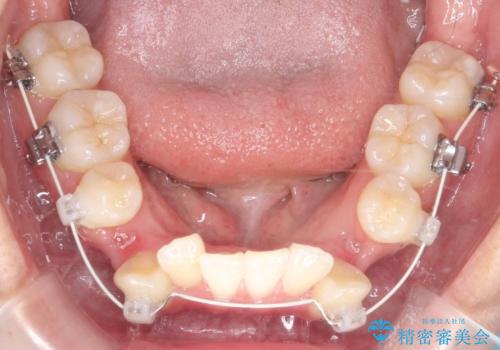

【ワイヤー矯正】八重歯 歯のでこぼこを治したい!

- 治療計画

- 「歯のでこぼこを治したい」を主訴に来院された患者様です。 上下ともに、歯のでこぼこが強く、上下左右4の抜歯をし、ワイヤー矯正で治療を行いました。

叢生量がかなり多かったのですが、歯肉退縮も失活歯も無くとても綺麗な歯並びになりました。